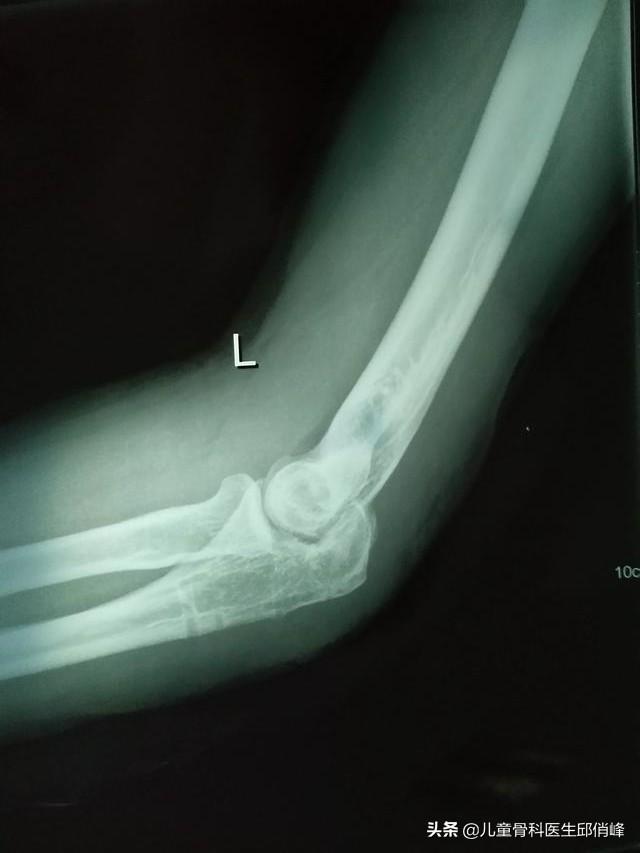

感谢邀请,从片子上看,应该是尺骨鹰嘴骨折手术后,骨折已经愈合,现在拆了钢板的。

从片子上看,肱尺关节,尺骨一侧的关节面模糊,毛糙,关节功能是会受到影响的。